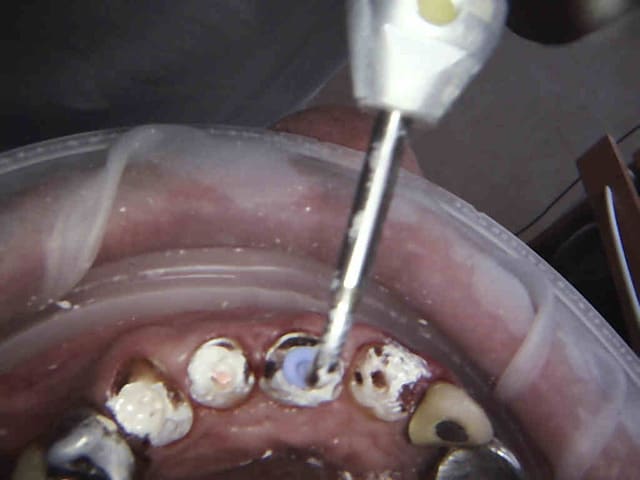

Endo taille empreinte provisoires 2H 30.

Gutta scellée au tubuli seal avec ou sans condensation thermo mécanique.

Logement du tenon réalisé au friendo ( voir photos) qui fond la gutta ( 200 ° au niveau de l'insert) . Un coup de machtou et hop tu peux passer les forets.

Avantage tu peux faire les provisoires et l'empreinte dans la séance et surtout tu peux raser les couronnes ce qui est un réel plus pour les endos surtout avec des pulpes rétractées comme ici ca évite de faire des conneries avec un abord palatin ou on ne voit rien du tout.

A 200 ° le plugger heater le ciment de scellement de cone tubuli seal prend fissa. Et pas de spray. ( logement fait avant l'obturation au largo puis la gutta thermocompactée de la longueur du tenon est virée au plugger heater , reste à passer un foret pivomatic). En un temps ca permet de raser les antérieures avant de faire l'endo, ca dégage le champ de vision et on centre mieux pour atteindre la pulpe meme rétractée.